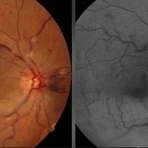

BRAO with CRVO (1 file)

BRAO with CRVO (1 file)